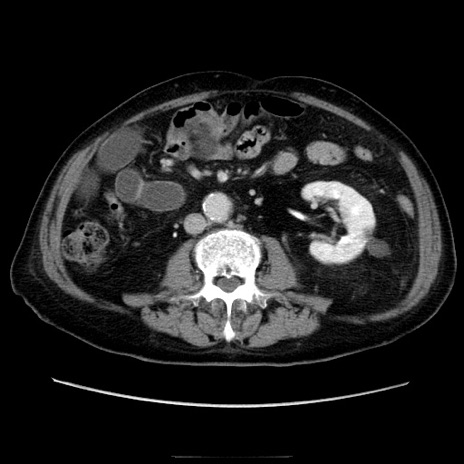

症例21(横断像)

【症例】70歳代男性

【主訴】腹痛

【現病歴】肝硬変・肝細胞癌にてかかりつけの方。約9時間前に食後より腹痛出現。症状が徐々に増悪し、嘔吐出現したため来院。

【既往歴】肝硬変、肝細胞癌(RFA、TACE後)

【身体所見】意識清明、表情苦悶様、BT 36℃、BP 129/78mmHg、P 88bpm、SpO2 97%(RA)、右上腹部から心窩部にかけて圧痛あり、反跳痛なし、筋性防御あり。

【データ】WBC 5800、CRP 0.16